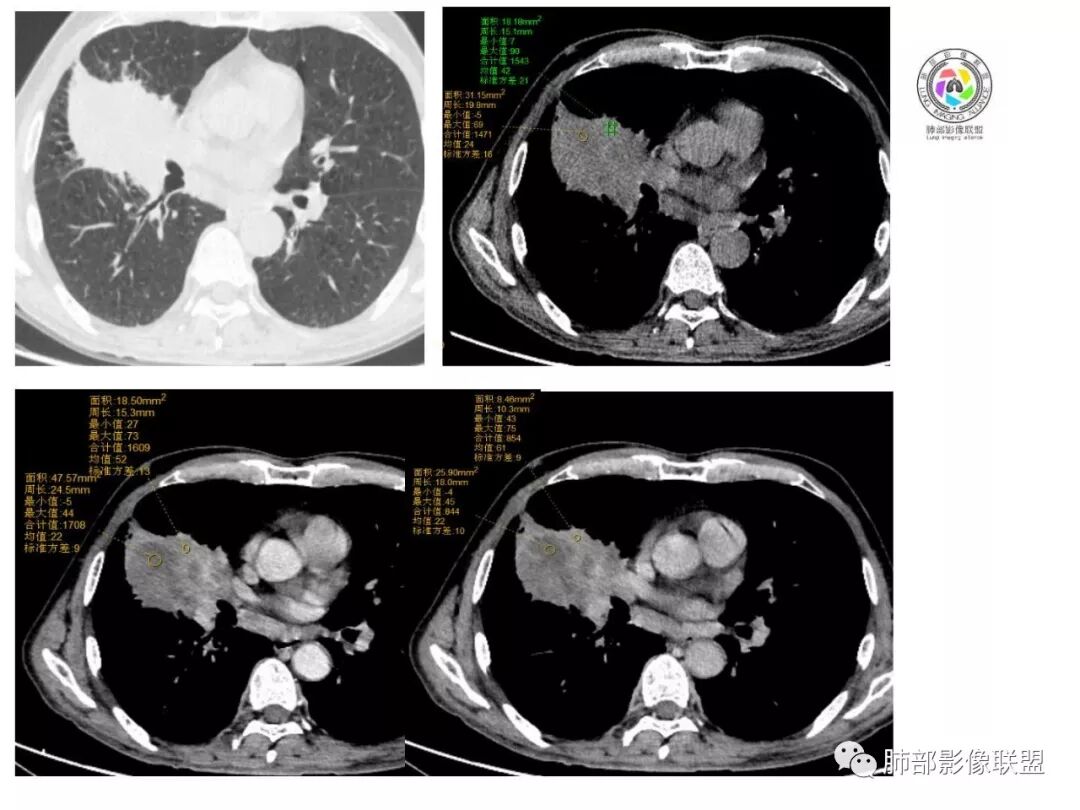

肺肉瘤样癌影像表现

影像表现缺乏特异性,CT最常见的表现是位于周围肺野的实质性肿块,病变部位以上叶多见,常位于胸膜下;

因为病灶有上皮成分和间叶成分,所以兼具肺癌和肺肉瘤的影像学特征,

1.具有肉瘤的特性:肿瘤体积一般较大,直径约大于5cm,边缘清楚、光整,由于肿瘤生长迅速,可见大片坏死,坏死边界清楚;常见支气管推移。

2.具有癌些特性:如分叶、短毛刺、空洞,但是钙化及胸膜凹陷征少见,病灶往往是直接侵犯胸膜,可以远处转移,肺门及纵隔淋巴结可明显肿大;

3.强化方式:增强后病灶以环状强化为主,病灶周边多以癌组织为主,血供丰富,病灶中心区则以肉瘤成分为主,血供较差,易出现粘液样变性、坏死、出血,坏死边界清楚,所以增强CT对PSC与普通型肺癌有一定的鉴别价值。

(中央型PSC肿块常位于肺门处,肿块多较大,边界较光整,伴有阻塞性肺炎或肺不张,与常见类型肺癌不易鉴别。)

病例小结

1.本病例结合病理结果及影像综合分析,应该符合肉瘤样癌,上皮成分是腺癌为主;肿块的边缘毛刺、分叶及周围癌型淋巴管炎征象有符合腺癌的影像表现之处。

2.肿块巨大局部边缘膨隆、光整,坏死较彻底;明显跨叶生长(途经发育不全叶间裂或肺门,注意患者没有胸水),支气管阻塞伴推移等,这些更符合肉瘤的特性。

3.坏死区边界较清楚(皮囊样),环形强化明显,病灶内血管穿行等,都不符合我们常见的鳞癌。

4.肺肉瘤虽然也是肿块巨大,呈大片状坏死,但是边缘光整圆隆,没有分叶、毛刺征象,较少出现肺门及纵隔淋巴结转移。